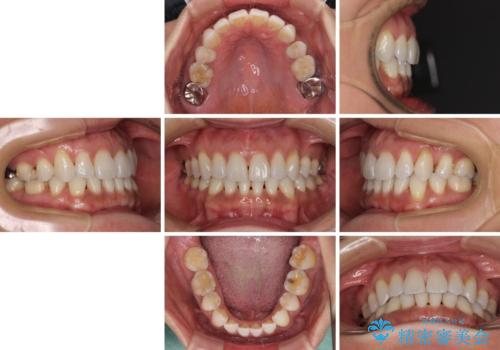

- 下顎前歯を中心に、以前行った矯正治療の後戻りが気になるとのことで来院された患者様です。

後戻りは軽度であったため、インビザライン・ライトにて治療を行うこととしました。

矯正治療後は、再度後戻りすることを極力回避するために、下顎前歯の舌側を細いワイヤーを用いて保定することとしました。